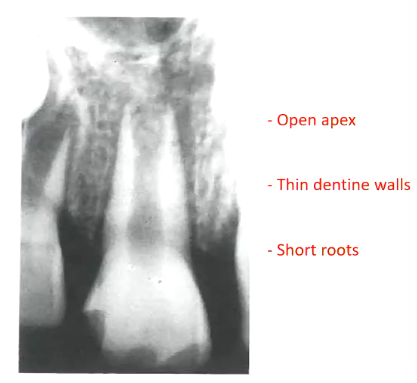

What are these series of radiographs showing?

the calcific barrier forming overtime and then oburation

What is this image showing?

different forms of hard tissue barriers

histologically all were cementum like

can be a ball on top, tin wall, rough